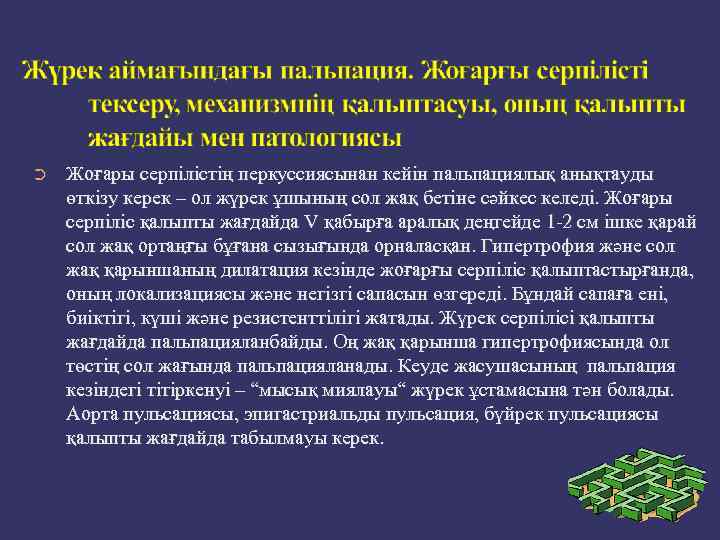

➲ Жоғары серпілістің перкуссиясынан кейін пальпациялық анықтауды өткізу керек – ол жүрек ұшының сол жақ бетіне сәйкес келеді. Жоғары серпіліс қалыпты жағдайда V қабырға аралық деңгейде 1 -2 см ішке қарай сол жақ ортаңғы бұғана сызығында орналасқан. Гипертрофия және сол жақ қарыншаның дилатация кезінде жоғарғы серпіліс қалыптастырғанда, оның локализациясы және негізгі сапасын өзгереді. Бұндай сапаға ені, биіктігі, күші және резистенттілігі жатады. Жүрек серпілісі қалыпты жағдайда пальпацияланбайды. Оң жақ қарынша гипертрофиясында ол төстің сол жағында пальпацияланады. Кеуде жасушасының пальпация кезіндегі тітіркенуі – “мысық миялауы“ жүрек ұстамасына тән болады. Аорта пульсациясы, эпигастриальды пульсация, бүйрек пульсациясы қалыпты жағдайда табылмауы керек.